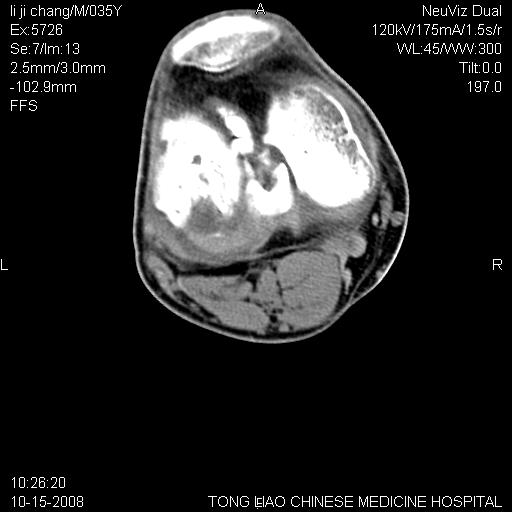

男,35岁,骨科诊断骨性关节炎。继往使用过激素,现股骨头坏死。膝关节病变,请会诊

一元论-----亦考虑为坏死

支持考虑无菌坏死

支持无菌坏死伴退行性骨关节病.

剥脱性骨软骨炎:是一种关节下软骨及软骨下骨缺血性坏死。

支持 无菌性坏死伴退行性骨关节病。